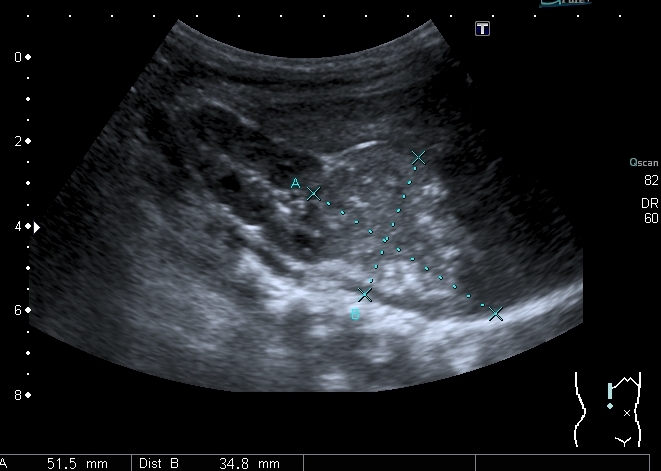

При УЗИ: печень резко увеличена, больше за счёт левой доли

Левая доля

Левая доля прилежит к селезёнке, оттесняет её вниз и дорзально

Паренхима печени -гиперэхогенная , неоднородная, практически полностью замещена нодулярными образованиями, некоторые из них с "гало" и кальцификацией